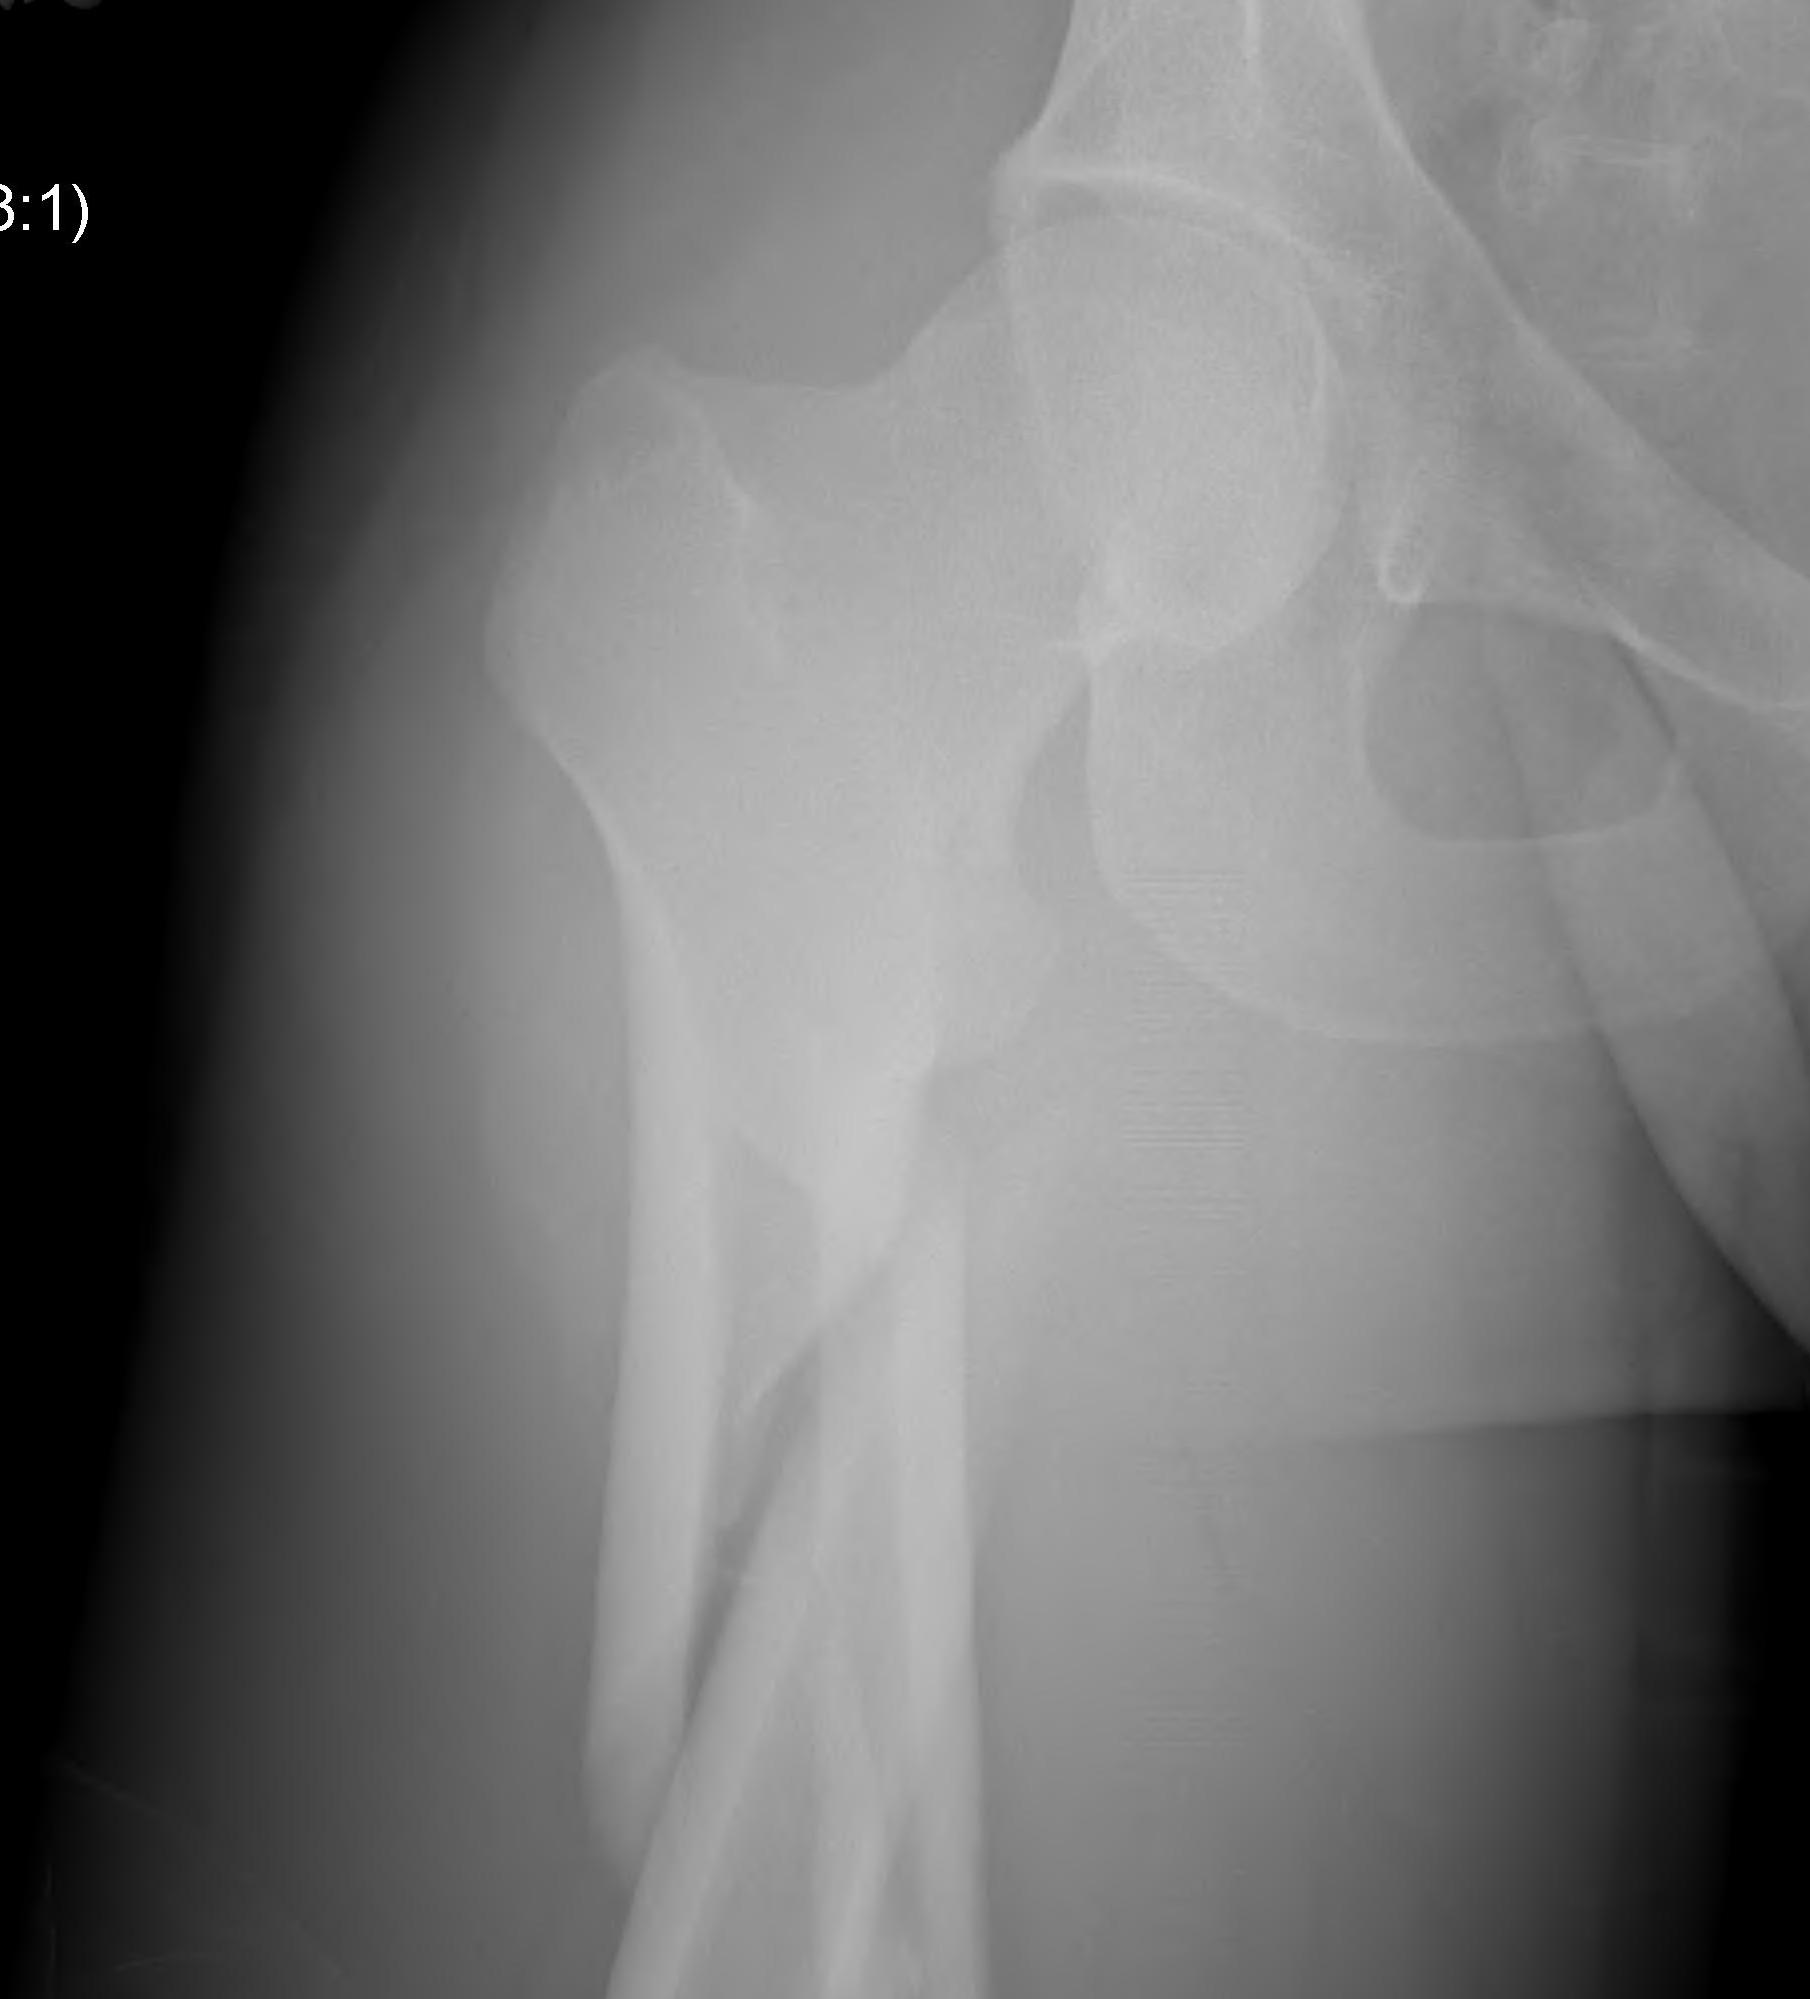

Hoffa fracture

Definition

Coronal plane fracture of distal femoral condyle

- intra-articular

- often only attachment is posterior capsule

Xray

Coronal plane fracture of distal femoral condyle

- intra-articular

- often only attachment is posterior capsule